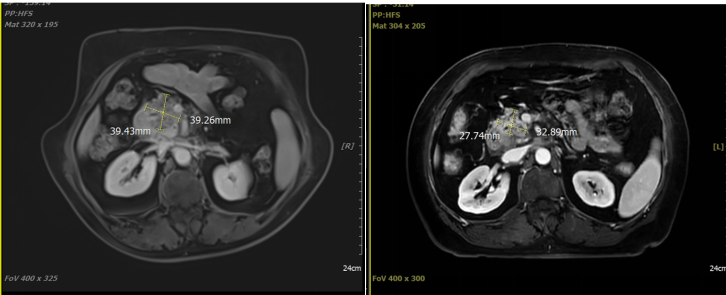

病例展示二:胰头恶性肿瘤

胰头部代谢增高灶,符合胰腺癌表现;伴腹主动脉周围淋巴结转移。侵犯门静脉及肠系膜上静脉,伴胰管及胆总管扩张。病理诊断:腺癌。cT3N1M1 Ⅳ期,KPS评分:80分。治疗方案:碳离子放疗:总剂量58.5Gy(RBE)/14Fx。同步化疗:吉西他滨+白蛋白紫杉醇。

影像学对比

治疗前(2025-3-5) 治疗结束后复查(2025-4-10)